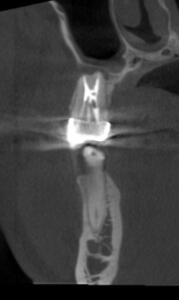

Клинические случаи в эндодонтии